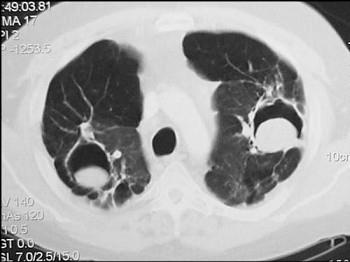

问题 男,48岁,发热,咳嗽,咳痰,咯血,PPD(-),请结合图,最可能的诊断是 ( )

选项 A.肺癌 B.肺曲菌病 C.肺结核 D.肺炎 E.肺脓肿

答案 B